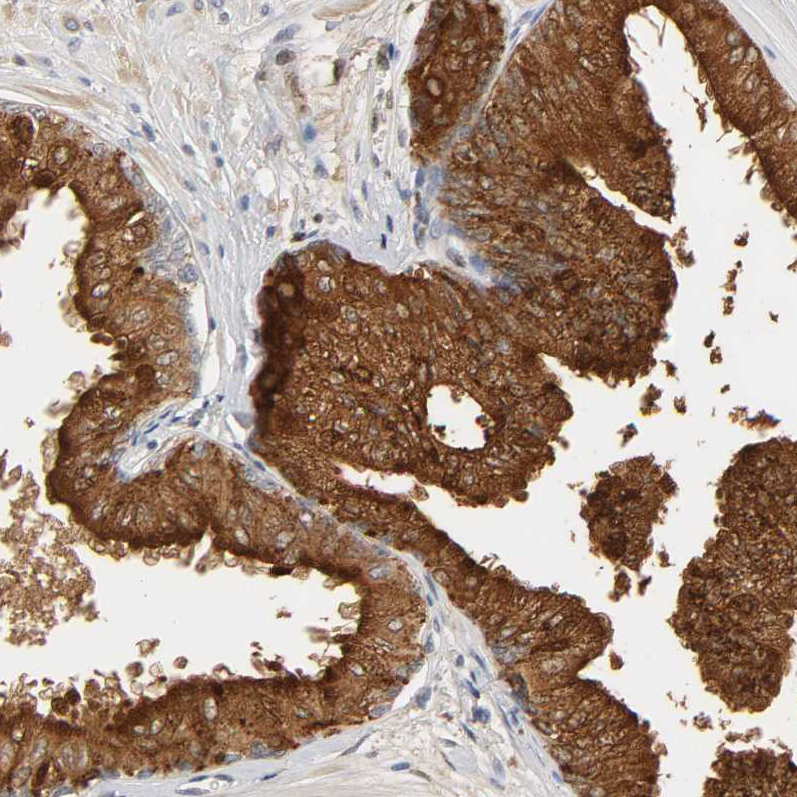

Immunohistochemistry analysis in human prostate and endometrium tissues using Anti-ACPP antibody. Corresponding ACPP RNA-seq data are presented for the same tissues.